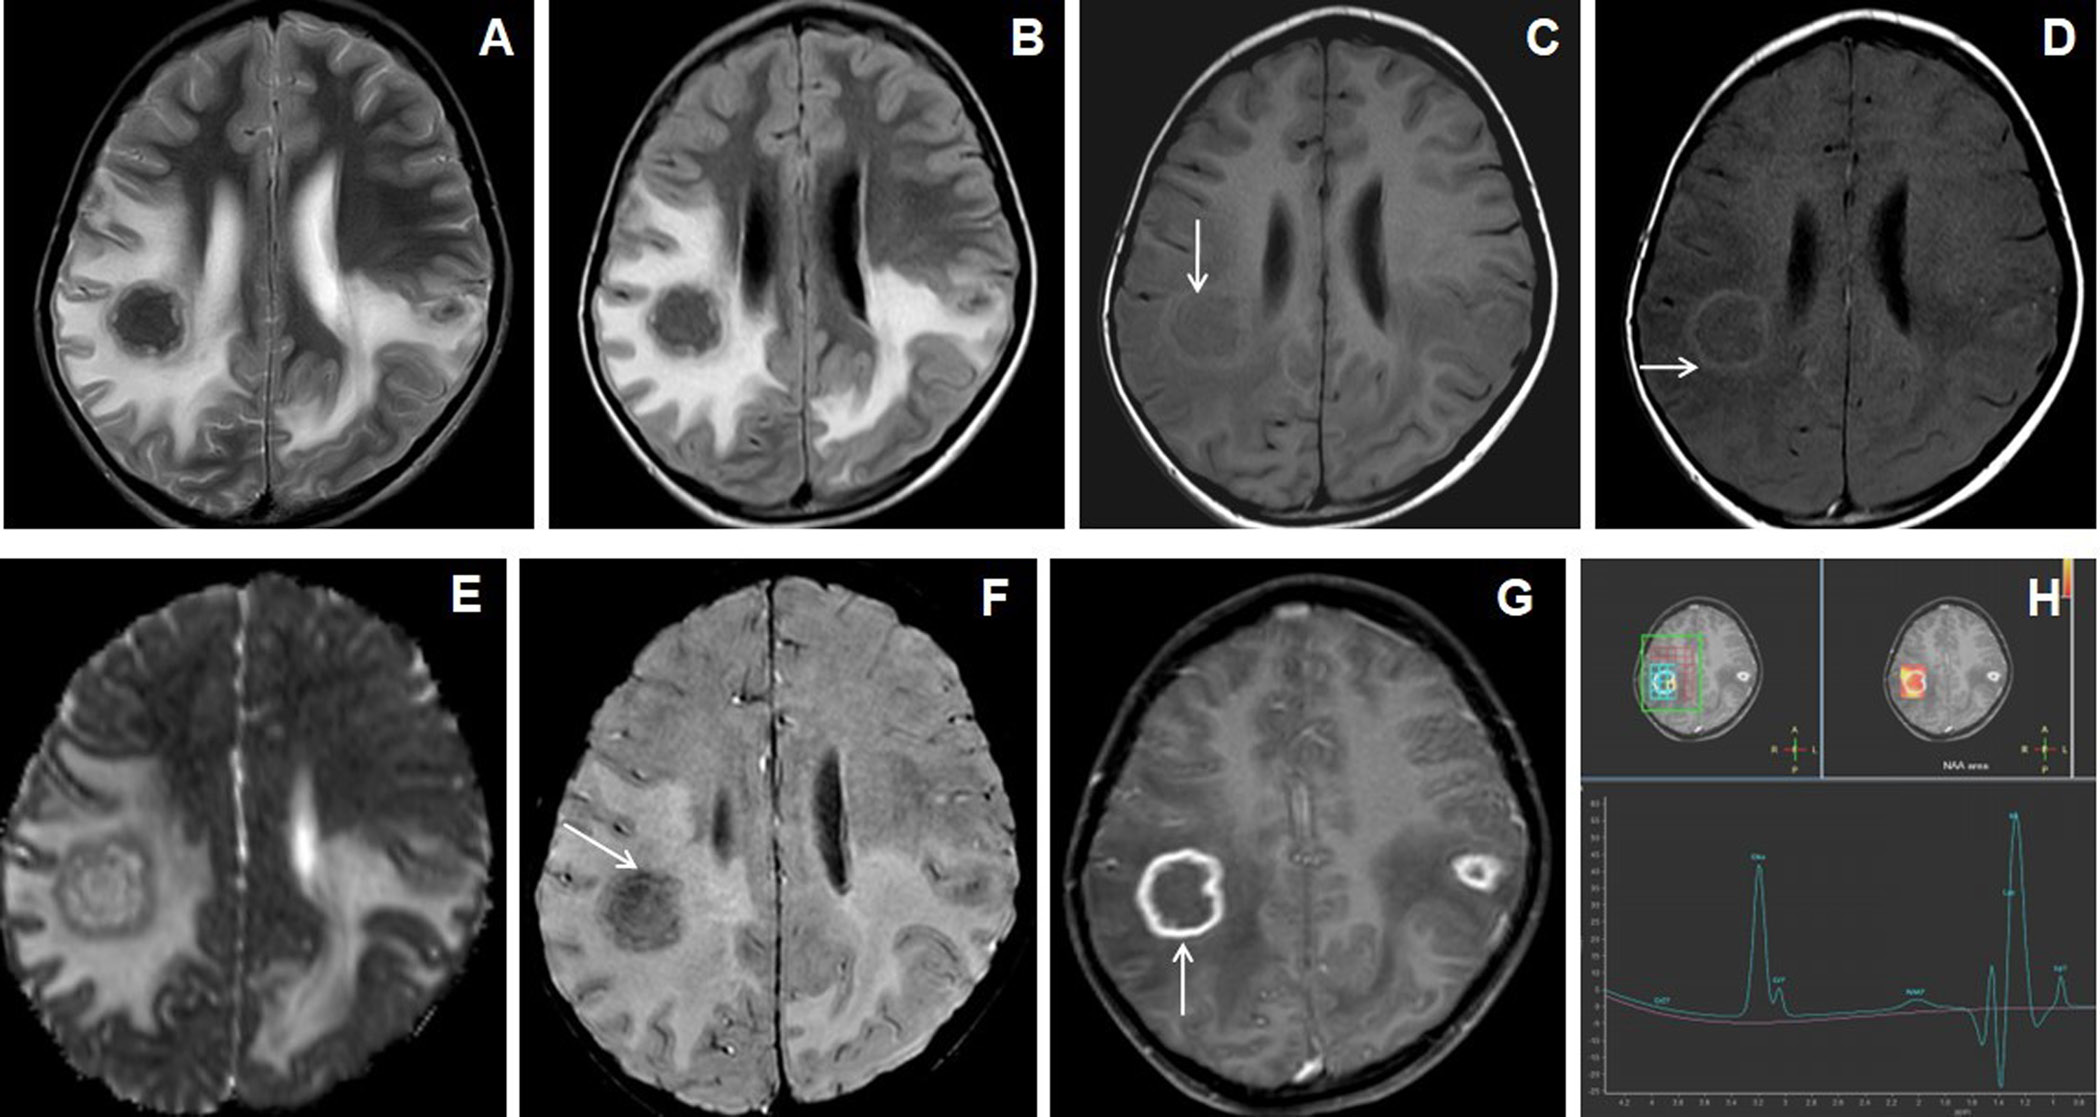

Figure 1. 7 years female presented with headache, vomiting and seizures. The axial T2W image (A) shows an irregular marginated T2 hypointense mass-like lesion in the right frontal lobe with grade-2 perifocal edema and associated mass effect. Axial T1W image (B) shows irregular peripheral T1 iso- to hyperintensities within the lesion (arrow). Axial and sagittal post-contrast images (C&D) show irregular shaggy peripheral wall enhancement of the lesion (arrow) with necrotic central core. The gross specimen (image E) shows the grayish-brown tissue of the lesion. 10X magnification microscopic examination (image F) shows caseous necrosis with epithelioid granulomas surrounded by lymphocytes.

Figure 2. 11 years male presented with headache, vomiting and seizures. Axial T2W and FLAIR images (A & B) show nodular lesions with central T2 hypointense core and isointense peripheral wall in the bilateral parietal lobes with grade-3 perifocal edema. Axial T1W image (C) showed isointense central core and hyperintense peripheral wall (arrow). Axial magnetization transfer (MT) image (D) shows a positive MT effect with bright signals within the wall of the nodular lesions(arrow). Axial ADC map image (E) shows slight peripheral wall diffusion restriction with low ADC value and facilitated diffusion in the core. Axial SWI image (F) shows blooming of hemorrhages in the peripheral wall (arrow). Axial post-contrast image (G) shows irregular shaggy peripherally enhancement of the lesions with central necrosis (arrow). MR spectroscopy (TE 144) image (H) shows a large lipid-lactate peak at 1.3ppm with raised choline peak.